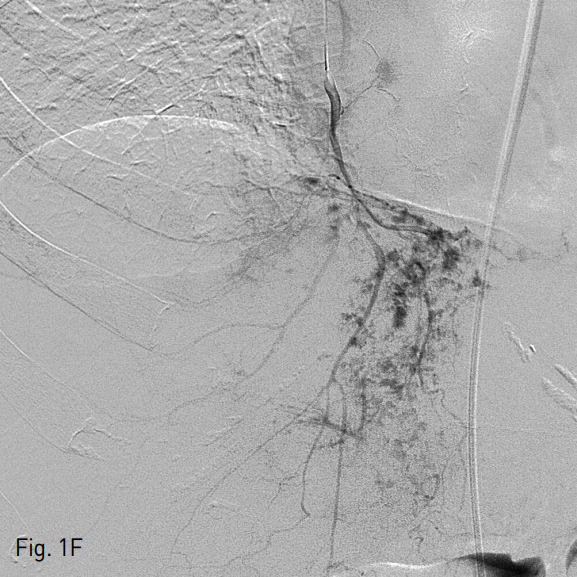

응급실 내원 직후 시행한 복부 CT에서 liver의 4,7,8 segment에 다량의 혈종과 pseudomaneurysm 그리고 multiple active bleeding이 관찰되었다 (Fig.1A). 색전술을 위하여 시행된 혈관조영술에서 replaced right hepatic artery branching off of the SMA를 통한 간 우분절에 다발성의 점상출혈이 있고 (Fig. 1B) 또한 left hepatic artery of celiac trunk를 통한 간 좌분절에도 다발성의 점상출혈이 있어 (Fig. 1C) 색전술을 시행하였다.

A. A initial contrast enhanced CT scan showed diffuse hepatic contusion of liver with large amount of intrahepatic hematoma and multifocal punctate extravasation of the contrast media, mainly at the segment 4 and 8 of liver. And there is large amount of hemoperitoneum in perihepatic and perisplenic space.